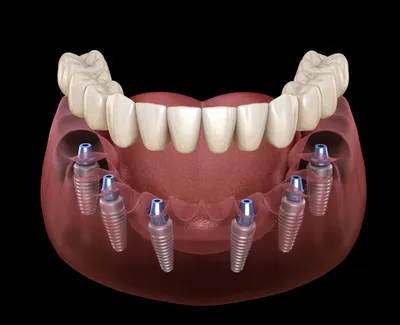

La technique On all 4 permet de reconstituer une arcade complète fixée sur 4 implants dentaires.C'est une solution rapide effectuée dans la journée et économique.Le Cabinet du Dr Tourrolier est spécialisé dans ce type de technique.

Implantologie exclusive All-on-4® et All-on-6® : le sourire fixe en une journée grâce aux technologies 3D et la chirurgie guidée.

Implantologue expert All-on-4® et All-on-6® : sourire fixe immédiat grâce à l’implantologie 3D, chirurgie guidée et esthétique immédiate.